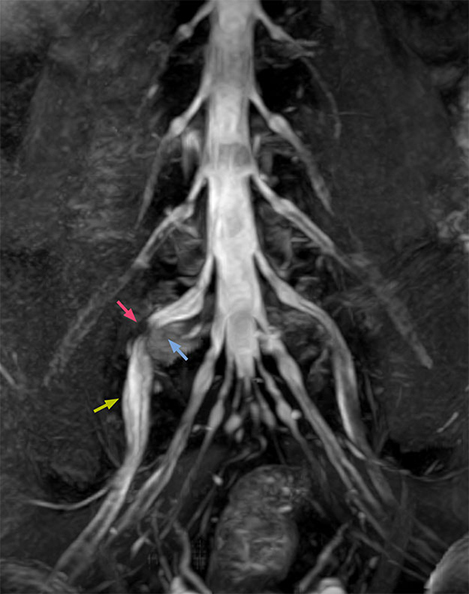

“In patients with lower extremity neurological symptoms, NerveVIEW helps us to determine the disease matching the patient’s symptoms by directly visualizing the nerves. We use the sequence mainly, when there is suspicion of intraforaminal stenosis, extraforaminal stenosis or lateral disc herniation, which is often based on routine T2- and T1-weighted images. Additionally, the excellent depiction of the course of nerves makes NerveVIEW a good navigator when applying treatment such as block therapy or surgery.”

The key concept in MR neurography, Dr. Yabuki stresses, is the ability to directly visualize spinal nerves, versus inferring the presence of pathology indirectly. “Before NerveVIEW, we estimated compression of the nerve by looking for the presence or absence of fat signal on other MR images,” he says.

“For example, in sagittal images, when the presence of fat is observed in the intervertebral foramen, it suggests that there is a margin around the nerve. Similarly, the absence of fat indicates that the nerve is being compressed. So, we used to deduce nerve compression indirectly. With NerveVIEW, however, we can observe the condition of the nerves directly, regardless of the presence or absence of fat. We always prefer such direct observation of anatomy over having to make an inference about it.”

According to Tanji, methods such as ProSet FFE, STIR or 3D VISTA are anatomically nonselective because background signals, for instance from blood vessels, often interfere with nerves, which hampers evaluation of details, especially at the peripheral side of the nerves.

“The intra-luminal signal of veins, especially around the intervertebral space, can be suppressed well with NerveVIEW. As a result, we can easily observe the detailed nerve structure around the posterior ganglion,” he says. “This is why we use 3D NerveVIEW for intraforaminal stenosis and extraforaminal stenosis/herniation (lateral disc herniation). On the other hand, if herniation is suspected to exist inside the dorsal root ganglion (DRG), balanced TFE or ProSet-FFE is applied. NerveVIEW is not suitable for evaluating the median type of herniation.”